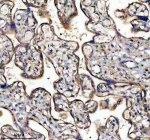

Immunohistochemical staining of TNS4 using anti-TNS4 antibody. TNS4 was detected in a paraffin-embedded section of human placenta tissue. Heat mediated antigen retrieval was performed in EDTA buffer (pH 8.0, epitope retrieval solution). The tissue section was blocked with 10% goat serum. The tissue section was then incubated with 2 ug/ml rabbit anti-TNS4 antibody overnight at 4oC. Peroxidase Conjugated Goat Anti-rabbit IgG was used as secondary antibody and incubated for 30 minutes at 37oC. The tissue section was developed using an HRP secondary and DAB substrate.